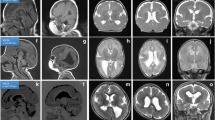

Nevertheless, irrespective of the type of lissencephaly (classical or variant) observed, some supratentorial and infratentorial abnormalities remain below the limits of resolution of MRI and are only detected by careful postmortem neuropathological examination (Fig. 1).

Ultrasonographic and MRI findings in the different type I lissencephaly subtypes: a Ultrasonographic pattern of MDS showing complete agyria with hypoplastic frontal lobes and dysmorphic corpus callosum and septum pellucidum (arrowhead). b, c MRI data in a DCX-mutated fetus displaying lissencephaly with moderate ventricular dilatation but no apparent infratentorial anomalies. d MRI performed at postnatal day 2 in a male newborn with XLAG syndrome, exhibiting pachygyria, more severe in the anterior regions and corpus callosum agenesis but with no infratentorial lesions. e MRI pattern on sagittal plane in a fetus with lissencephaly and cerebellar hypoplasia (genetic cause unknown). The corpus callosum is normal (thin arrow). The vermis is rudimentary and unfoliated, the primary fissure being absent. The brainstem is moderately hypoplastic (thick arrow). f MRI in a TUBA1A-mutated female fetus, showing severe microcephaly and ventriculomegaly. The vermis is hypoplastic especially in its inferior part, but remains foliated (g). The pons and medulla are severely flattened (arrow, g)